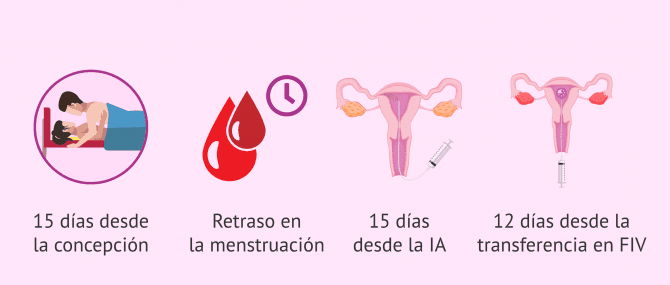

Cuando hacer la prueba de embarazo DKV- en 14 dias puedo saber si estoy embarazada

- 15 dias despues de tener relaciones puedo saber si estoy embarazada

- a los cuantos dias despues de tener relaciones se si estoy embarazada